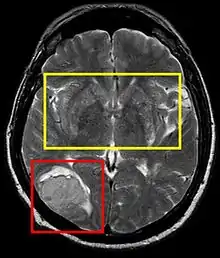

| Stroke brain (similar to cerebral softening) | |

Cerebral softening, also known as encephalomalacia, is a localized softening of the substance of the brain, due to bleeding or inflammation. Three varieties, distinguished by their color and representing different stages of the disease progress, are known respectively as red, yellow, and white softening.[1][2]